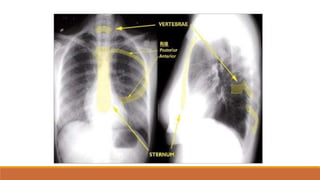

Khung xương

2/ Xương lồngngực

- Xương sườn

- Xương ức

- Cột sống ngực

- Xương vai

- Xương đòn